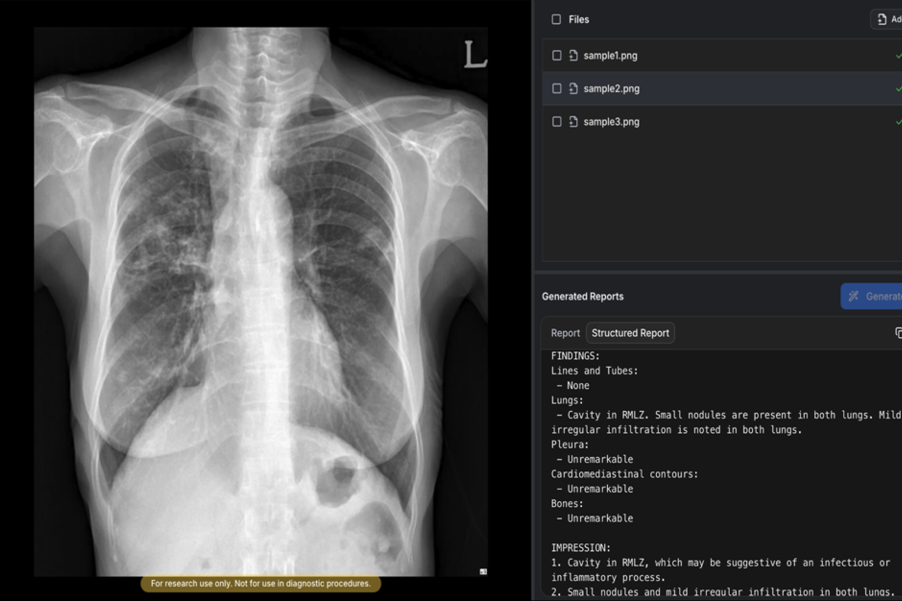

2일 숨빗AI는 자사의 흉부X선 예비소견서(Draft Radiology Report) 생성 솔루션 'AIRead-CXR'(에어리드-씨엑스알)가 식약처 3등급 인허가를 획득했다고 밝혔다.

AIRead-CXR은 국내외에서 확보한 약 1400만건의 데이터를 학습해, 다양한 병원 환경에서 촬영된 PA 또는 AP 흉부X선에 대해 안정적으로 예비소견서를 제공한다.

핵심적으로 검증된 57개 소견 및 질환에 대해 높은 수준의 판독보조 성능을 제공할 뿐 아니라 이 외의 다양한 영상 소견도 해석·언급할 수 있다. 실제 임상 현장의 워크플로우를 반영해 의료진이 보다 효율적으로 판독 업무를 수행할 수 있도록 설계됐다.

품질 경쟁력도 주목된다. 공개된 임상 논문에 따르면, 흉부영상 전문의들이 평가한 AI 예비소견서 평균 수용도는 85%로, 비교 대상인 MedGemma(66.9%)를 상회했다.

생성형 AI의 대표적 한계인 환각(hallucination) 비율 역시 0.3%로, MedGemma(9.7%) 대비 우수한 안정성을 보였다. 이런 기술력과 임상적 유효성은 영상의학 분야 최고 권위 학술지인 Radiology에 3편, AJR에 1편 이상의 논문으로 뒷받침되고 있다는 게 사측 설명이다.